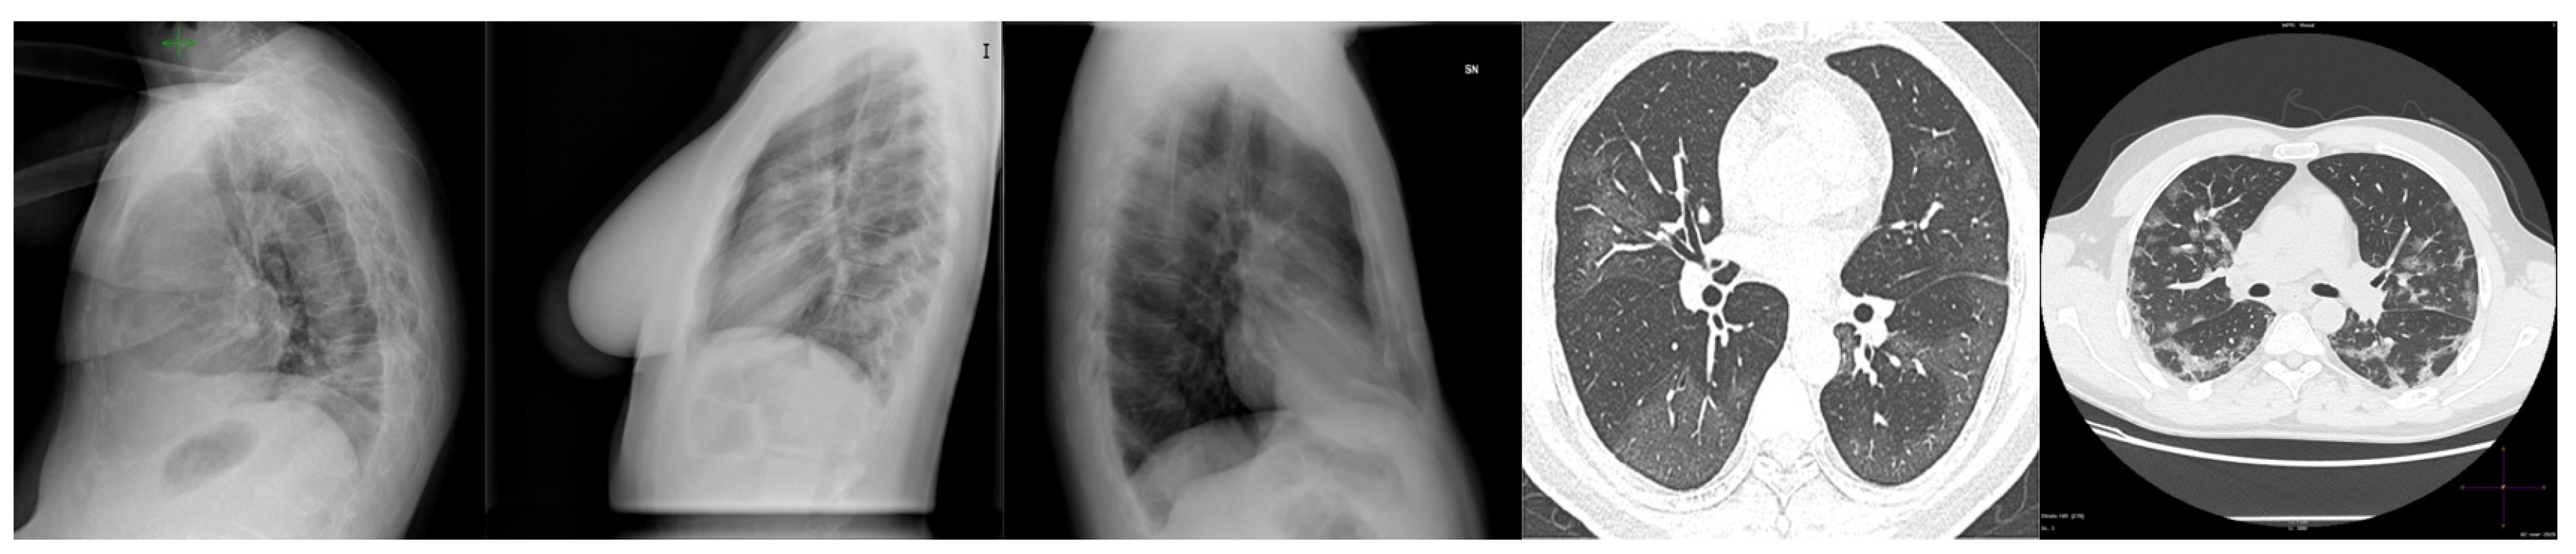

3.1. Chest X-ray Dataset

| Abdani et al. [2] | SPP-COVID-Net | • Applies spatial pyramid pooling module to extract features of various scales. | • The experiment has included X-ray images taken from a side view for COVID-19 cases, which will give advantage for that class detection performance. |